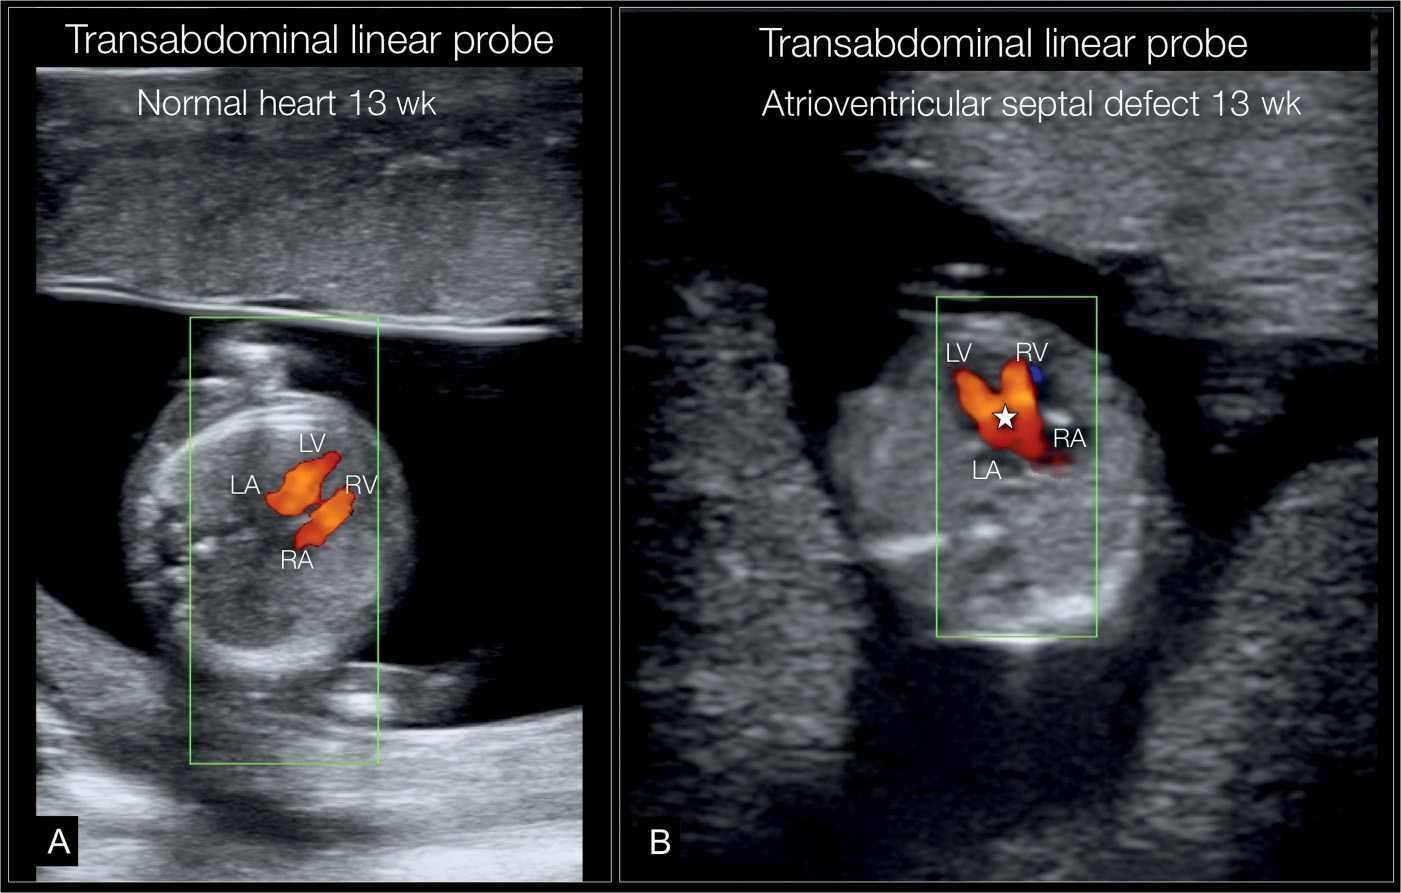

From obgynkey.com

Fetal Cardiac Examination in Early Gestation Obgyn Key Heart Block Fetus Complete heart block affects about 1 in 20,000 pregnancies. Complete heart block is a disorder of the heart’s electrical system, which controls the rate and rhythm of heartbeats. In acquired heart block, block is distal to av node, heart rate is usually 40 or less per minute with wide qrs in ecg. In some cases, no cause is found to. Heart Block Fetus.